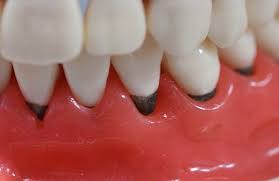

잇몸이 소실되는 가장 흔한 원인은 바로 **치주 질환**입니다. 치주 질환은 치아 주위 조직에 염증이 생기는 질환으로, 초기에는 잇몸이 붓고 피가 나는 치은염으로 시작해, 점차 잇몸뼈까지 녹아내리는 치주염으로 발전합니다. 치주염이 심해지면 잇몸이 내려앉아 치아 뿌리가 노출되고, 결국 치아를 지지하는 잇몸뼈가 소실되어 치아가 흔들리거나 빠질 수도 있습니다.

잘못된 양치 습관도 잇몸 소실의 주범이 될 수 있습니다. 너무 세게 칫솔질을 하거나, 뻣뻣한 칫솔모를 사용하는 경우 잇몸에 과도한 자극을 주어 잇몸 퇴축을 가속화할 수 있습니다. 또한, 치아 교정 후나 노화로 인한 자연스러운 잇몸 퇴축도 무시할 수 없는 원인 중 하나입니다.